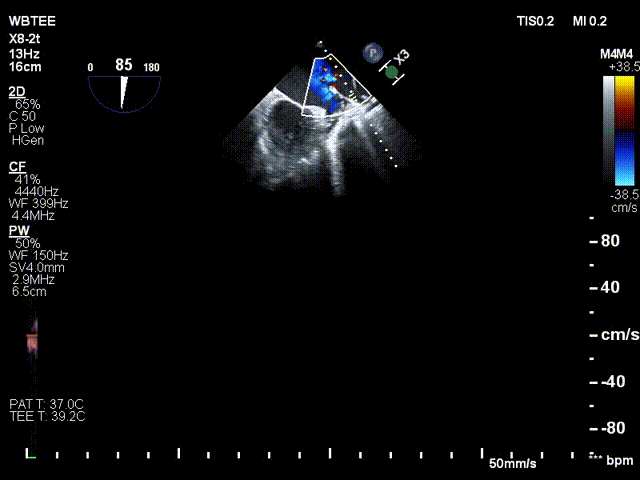

术前行经食道超声评估

原发性二尖瓣反流,反流程度4+;二尖瓣瓣口面积4.15cm²,平均跨瓣压差5mmHg,二尖瓣前叶(A2)长度23.35mm,二尖瓣后叶长度(P2)长度13.2mm;左室射血分数67%。患者手术风险高,操作难度大,经心脏瓣膜团队多次充分讨论评估后,决定行经导管二尖瓣缘对缘修复治疗。

术前MDT策略:从解剖结构来看二尖瓣后叶脱垂伴连枷涉及整个2区,累及3区和1区,宽度15mm左右,且连枷高度甩起高度有7-8mm,可见长达10.4mm的飘样回声,术前策略预计使用两个二尖瓣夹,较小的二尖瓣口面积和较高平均跨瓣压差,是一次高难度的挑战。